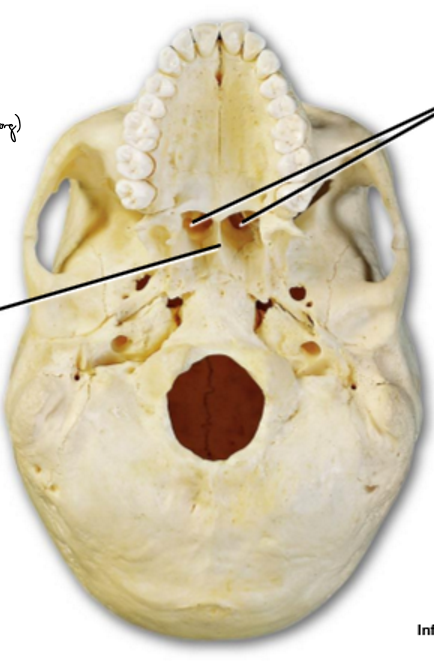

A-D

A: Nares (nostrils)

B: Choanae (posterior nares)

C: Superior, middle, inferior nasal conchae

D: Meatus

The ______ open into nasopharynx

choanae

Medial wall formed by ______

Nasal septum

Lateral walls include _________ with intervening ______-

Nasal conchae, meatuses

Superior, middle, inferior nasal conchae

Superior, middle, inferior meatuses